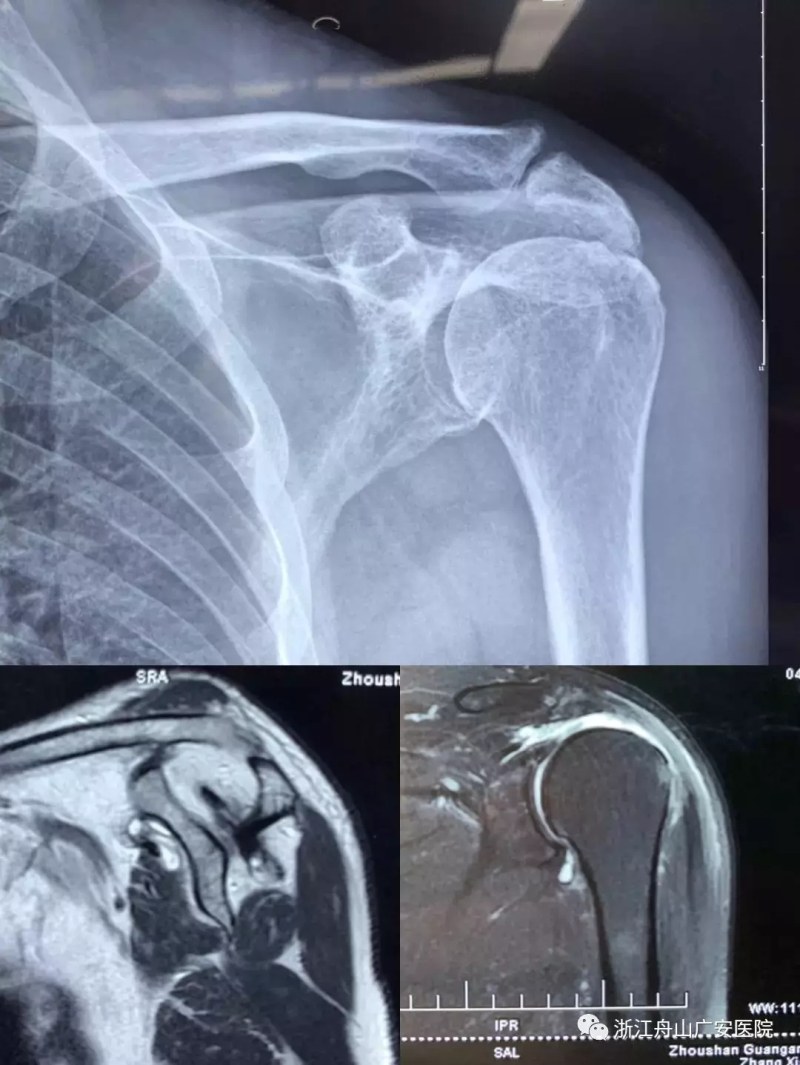

張大伯一年前因右肩巨大肩袖斷裂,曾在我院行關(guān)節(jié)鏡微創(chuàng)手術(shù),術(shù)后恢復(fù)非常滿意?,F(xiàn)患者要求進(jìn)一步行左肩關(guān)節(jié)手術(shù)治療入院,經(jīng)過(guò)廣安醫(yī)院常務(wù)副院長(zhǎng)危立軍、關(guān)節(jié)科及運(yùn)動(dòng)醫(yī)學(xué)科羅軍主任的詳細(xì)檢查,患者為左肩巨大不可修復(fù)肩袖撕裂關(guān)節(jié)病,肩袖的脂肪浸潤(rùn)達(dá)到四級(jí),常規(guī)的微創(chuàng)手術(shù)治療不能恢復(fù)患者的肩膀功能,只能通過(guò)特殊類型的人工肩關(guān)節(jié)——反式全肩人工關(guān)節(jié)來(lái)重建關(guān)節(jié)功能。

反式肩關(guān)節(jié)置換術(shù)后照片